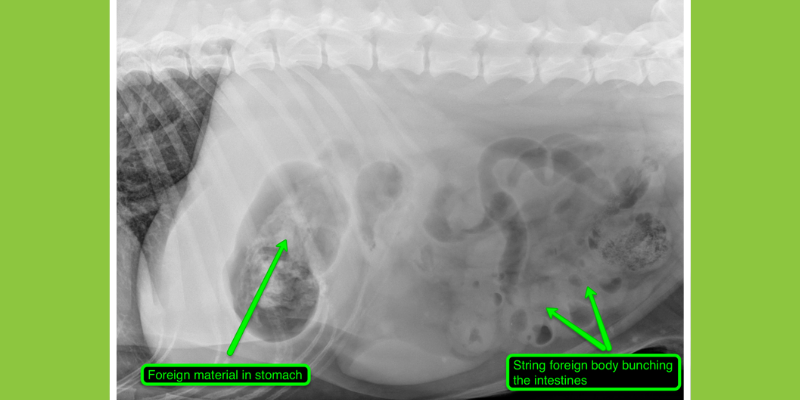

Ultrasound

An ultrasound is used to get a live view of what’s going on inside your pet’s body. This imaging option provides superior detail within the abdomen as well as some chest structures like the heart or mediastinum. While an x-ray often only provides an outline or silhouette of abdominal organs, an abdominal ultrasound is more accurate in evaluating their internal structure. However, ultrasound is limited to soft tissue structures and cannot image through air filled structures or bone. Ultrasound is performed frequently in awake pets or pets with varying degrees of sedation.

Abdominal ultrasounds are commonly recommended following abnormal or concerning x-rays to better define a disease process. Common reasons to conduct an ultrasound include concern for gastrointestinal obstruction, chronic inflammatory disease, or cancer, as well as elevated liver or kidney values, anemia, or suspected metabolic conditions. Our board-certified specialists will also often recommend baseline and recheck ultrasounds to monitor response to therapy for cancer or inflammatory diseases.

Ultrasound image of the intestines in a cat. The intestinal wall is thickened with abnormal layer distribution with the appearance highly typical of inflammatory bowel disease or occasionally a cancer called small cell lymphoma. These layer changes are not visible on x-rays.